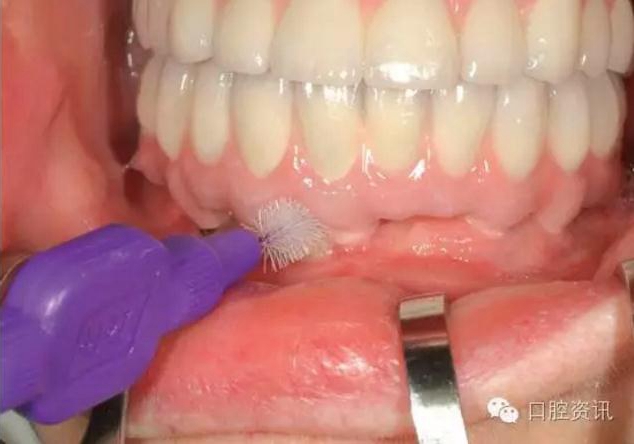

我們也希望您可以保質(zhì)保量地進行口腔清潔,每日兩次刷牙、漱口以

及使用牙線、間隙刷等,都是最基本的要求。由于種植牙的構(gòu)造與天

然牙不同,有時您也需要一些特定的清潔工具。

16.jpg

圖16. 使用特制的間隙刷清潔